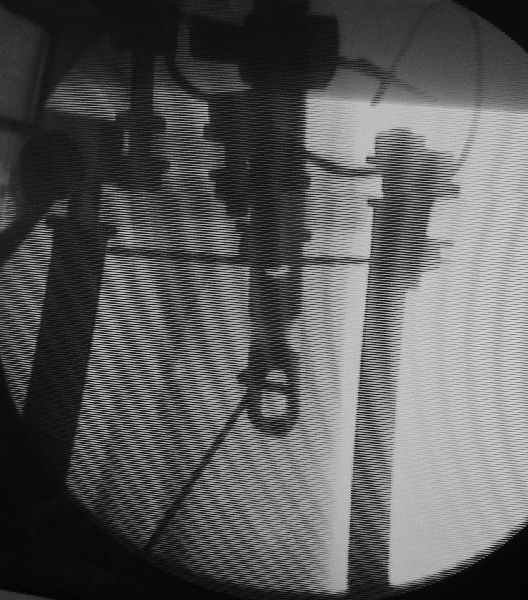

Вот картинка с ЭОП - гвоздь проходит центральный отломок, видно, как спица не дает ему отклониться к задней стенке канала.

Мы предпочитаем использовать отклоняющие спицы. Поищу картинку сответствующую. Их вводить быстрее и проще, чем винты. И если чересчур кпереди проведешь спицу, то она изогнется, но гводь пропустит. А с винтом гвоздь может зажать, или расколоть можно.

Это типично особенно для высоких переломов. Канал гвоздя в центральном отломке должен быть ближе к переднему кортексу. Poller винт или лучше спица проблему решают. Ну и гвоздь большего диаметра "автомагически" смещение бы устранил.